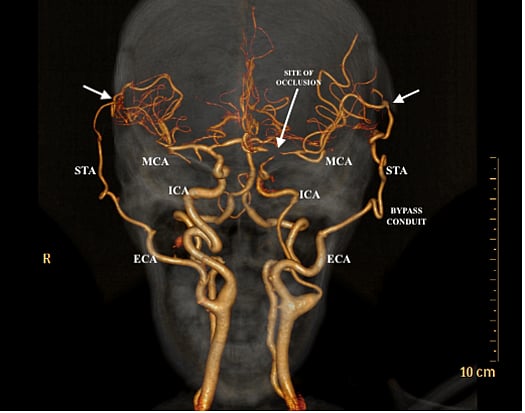

தற்போது வெற்றிகரமாக அறுவை சிகிச்சை முடிந்து சிறுமிகளும் நலமுடன் இருக்கின்றனர். இது போன்ற நிகழ்வு ஆசியாவிலே இது தான் முதல் முறை. தற்போது அவர்களது மூளையின் இடது பக்கத்தில் இரத்த ஓட்டம் மேம்படுத்தப்பட்டது ஸ்கேன்கள் மூலம் கண்டறியப்பட்டுள்ளது" என்றது.

மோயா மோயா நோய் என்றால், உடலில் உள்கழுத்துக்கு அடியிலும், முதுகுத்தண்டு வழியாகவும் மூளைக்கு இரத்தம் எடுத்துச் செல்லும் தமனிகள் உள்ளது. இந்த முக்கிய நாளங்கள், தலைக்குள் மூளையைப் பாதுகாப்பாக வைக்கும் மண்டையோட்டுக்குள் நுழைந்த பின்னர்தான் நாள அடைப்புகள் பாதிப்பு ஏற்படுகிறது.

அதனால், மூளைக்குப் போதிய அளவு இரத்தம் கிடைக்காமல், நோயாளிகள் மூளை அடைப்புக்கு உள்ளாகிறார்கள். இதனை ஈடுகட்டும் வகையில் மூளைக்கு அடியிலுள்ள நுண்ணிய ரத்தக்குழாய்கள் ஊதிப்பெரிதாகி, புதிய ரத்த ஓட்டத்திற்கான பாதையை உண்டாக்குகின்றன என்பது குறிப்பிடத்தக்கது.